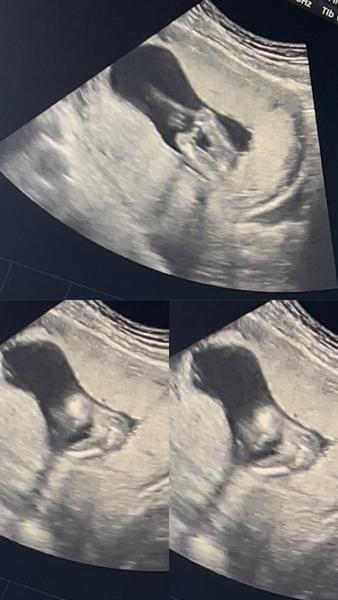

Jak poznat pohlaví dítěte podle ultrazvuku?

Jak se zjišťuje pohlaví dítěte?.

Určitě tě nemine 3D ultrazvuk.